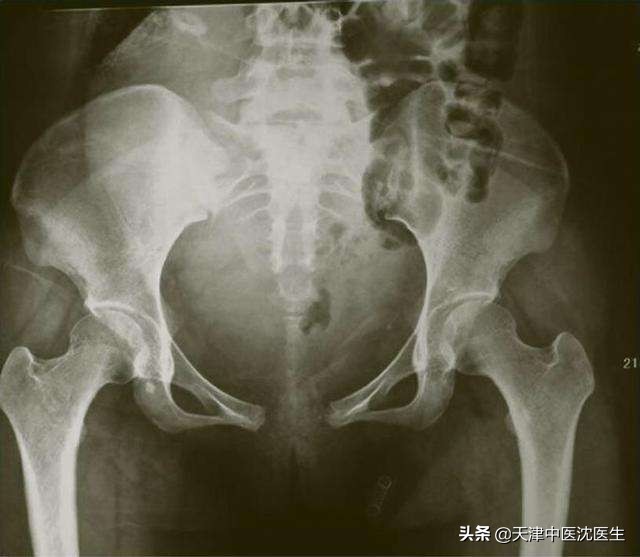

母亲是非常伟大的,分娩时要经历“开骨缝”也就是子宫口打开的过程,而因为体内分泌激素的缘故,耻骨联合的韧带从妊娠初期就开始慢慢变得松弛,正常耻骨联合距离为4-6mm,生育时可增宽至10mm,而间距进一步增大时,到了2cm,甚至3cm或以上,即为耻骨联合分离,类似于韧带的损伤,所谓伤筋动骨一百天,这个时候就要制动让其修复,但是长期卧床期间不仅是生理上的痛苦,还有心理上的痛苦,极易产生焦虑抑郁。

笔者在临床中接触的患者有些就是分娩时耻骨联合分离但是没有恢复好,导致耻骨联合对合不良从而引起骶髂关节紊乱,坐卧行走都苦不堪言。写下本文是因为有位外地的患者联系到我咨询,他是2020年1月28日分娩,耻骨联合分离2cm,不能行走,卧床休息但没有固定,现在2个月了耻骨酸胀感明显。俗话说亡羊补牢为时不晚,我们就来总结一下产后耻骨联合分离需要如何注意吧。